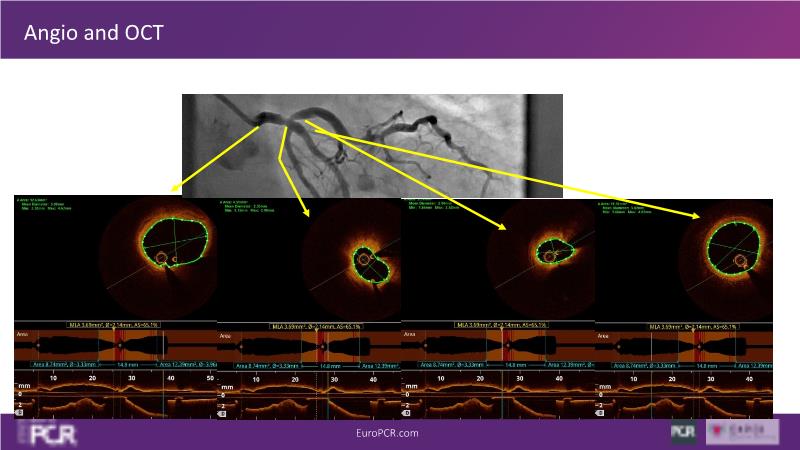

Rethinking PCI in left main: OCT-guided optimisation

Discover the transformative role of optical coherence tomography (OCT) in optimizing left main percutaneous coronary intervention (PCI) in this session. Gain insights into how OCT can guide the step-by-step process of left main PCI to achieve optimal results, and explore the crucial parameters of procedural outcome, stent selection, and patient profile for achieving a balanced antiplatelet therapy regimen.